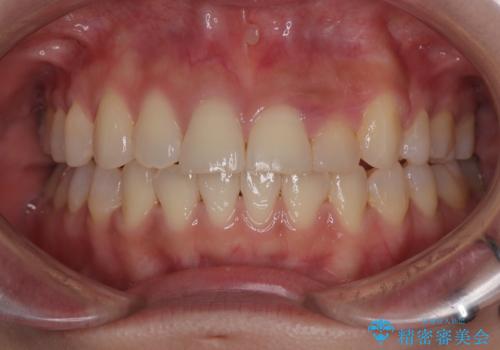

最新の症例

Latest cases